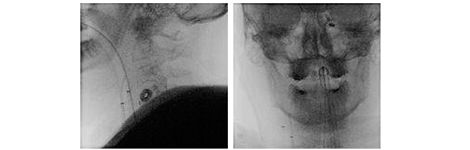

Off-isocenter imaging capability

Off-isocenter imaging allows you to see the vessels from two different centering positions with one injection in one fluoroscopic shot. For example, to verify the catheter position, you can simply move the lateral plane off-isocenter without changing or losing your frontal/AP plane position. You can visualize both the origin of the vessel (lateral) and the distal area (frontal/AP) with just one injection and one acquisition.

630benefits_Off-iosocenter